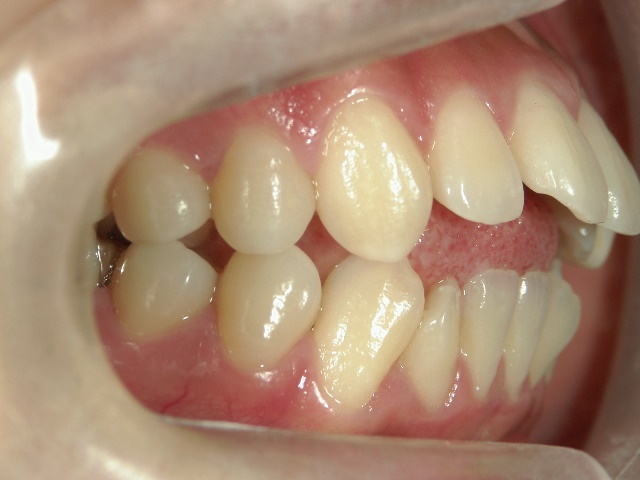

主訴:奥歯で噛んだときに前歯が噛み合わない

中学生になり第二大臼歯が生えてから、真ん中の前歯2本が出てきて、八重歯も目立つようになりました。はじめは八重歯がチャームポイントだと捉えて気にしていませんでしたが、年々歯並びが悪化している気がしました。そのうち前突が原因で口が閉じづらく、寝ている時は口呼吸になってしまいました。

高校時代には、歯並びを改善しようと様々な矯正サイトを閲覧し、自分自身が開咬であることを知りました。開咬とは、上下の歯を噛み合わせた時に前歯に隙間ができることを言います。そういえば、麺を前歯で噛みきること、ハンバーガーにガブッと噛みつくことができませんでした。

2年を少し過ぎたころには歯並びが良くなり、開咬もだいぶ改善されました。結婚式を予定していたため早期終了をさせていただきましたが、開咬が治ってハンバーガーをガブッと噛みきることができるようになって、とっても嬉しいです。式でもきれいな歯並びで、思いっきり笑うことができました。